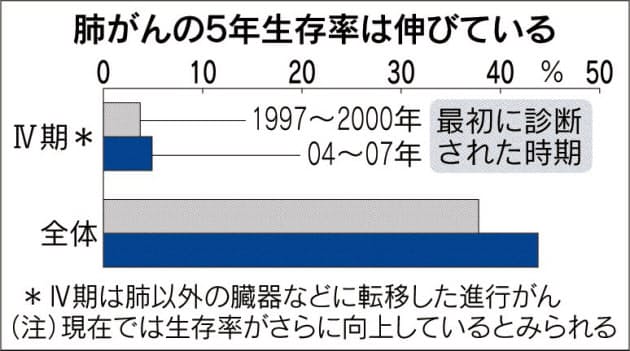

進行肺がん 新薬続々 分子標的薬や免疫薬 ヘルスup Nikkei Style